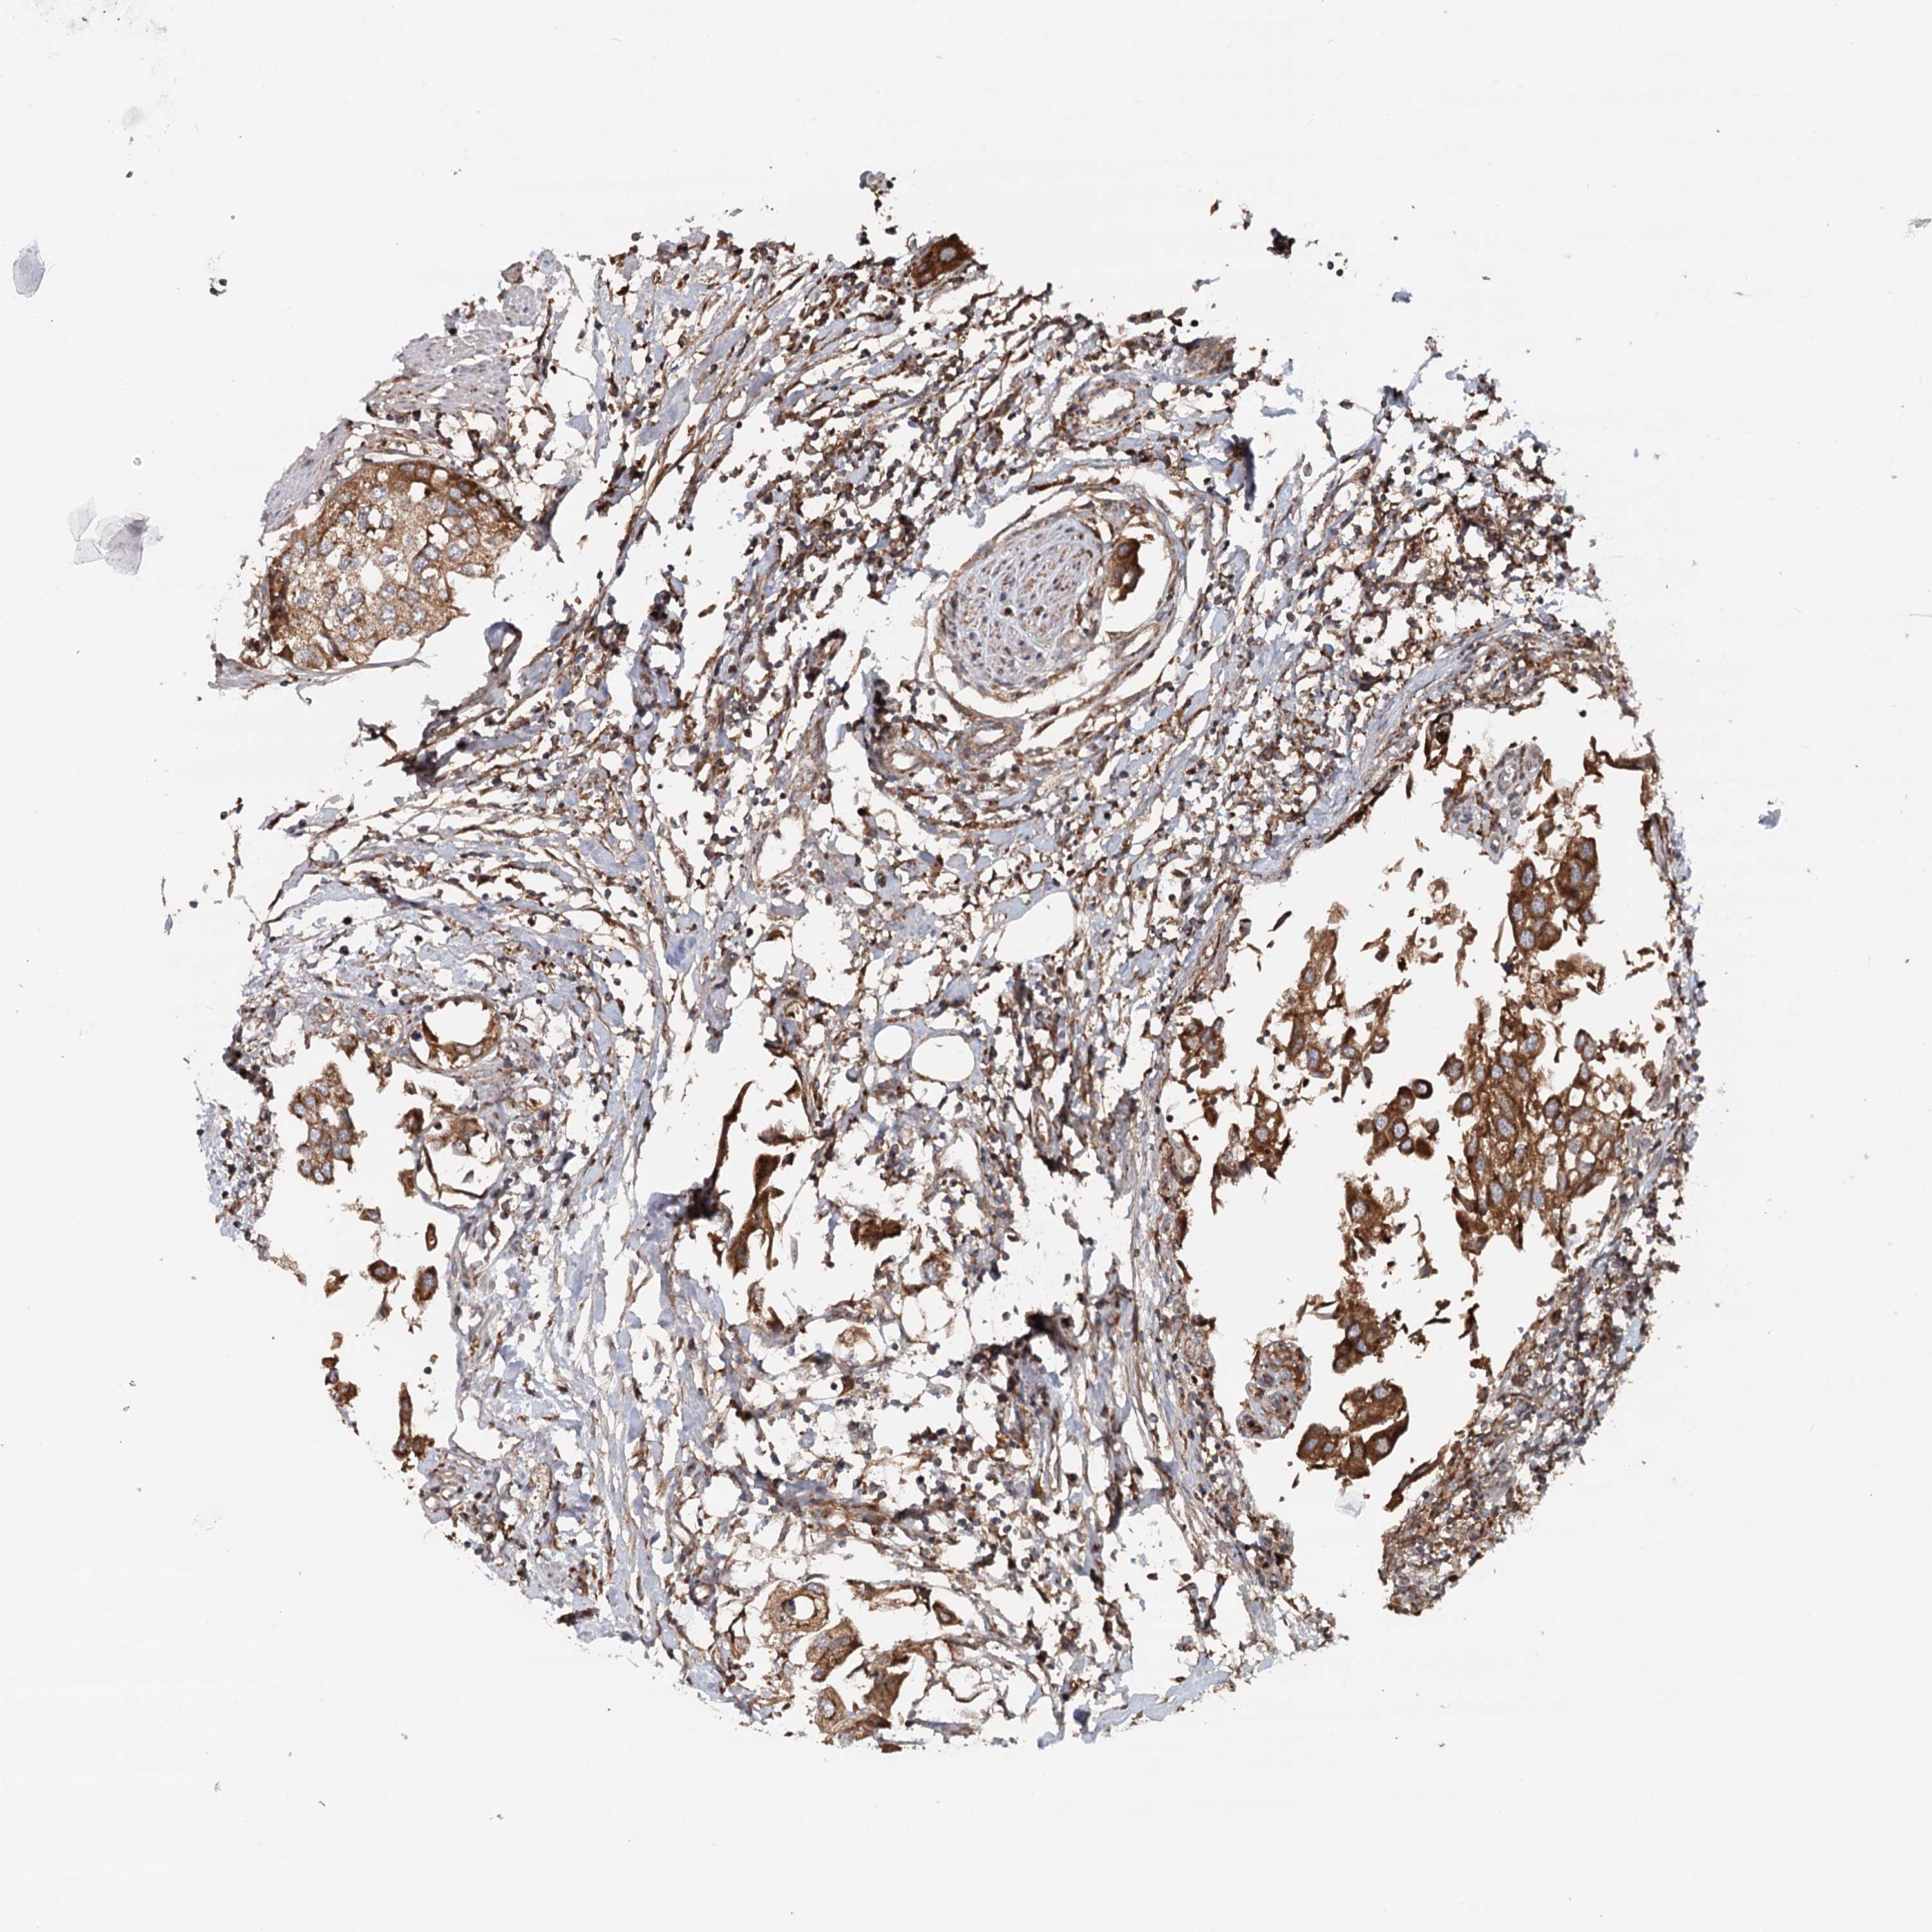

UROTHELIAL CANCER - Protein expressioni

A mouse-over function shows sample information and annotation data. Click on an image to view it in a full screen mode. Samples can be filtered based on level of antibody staining by selecting one or several of the following categories: high, medium, low and not detected. The assay and annotation is described here.

Note that samples used for immunohistochemistry by the Human Protein Atlas do not correspond to samples in the TCGA dataset.

Antibody stainingi

Antibody staining in the annotated cell types in the current human tissue is reported as not detected, low, medium, or high, based on conventional immunohistochemistry profiling in selected tissues. This score is based on the combination of the staining intensity and fraction of stained cells.

Each image is clickable and will lead to virtual microscopy that enables deeper exploration of all samples and also displays staining intensity scores, fraction scores and subcellular localization as well as patient and tissue information for each sample.

Antibody HPA038576

Antibody HPA038577

Staining

High

Medium

Low

Not detected

Intensity

Strong

Moderate

Weak

Negative

Quantity

>75%

75%-25%

<25%

None

Location

Nuclear

Cytoplasmic/membranous

Cytoplasmic/membranous,nuclear

Urothelial carcinoma, High grade

Urothelial carcinoma, Low grade

Urothelial carcinoma, NOS